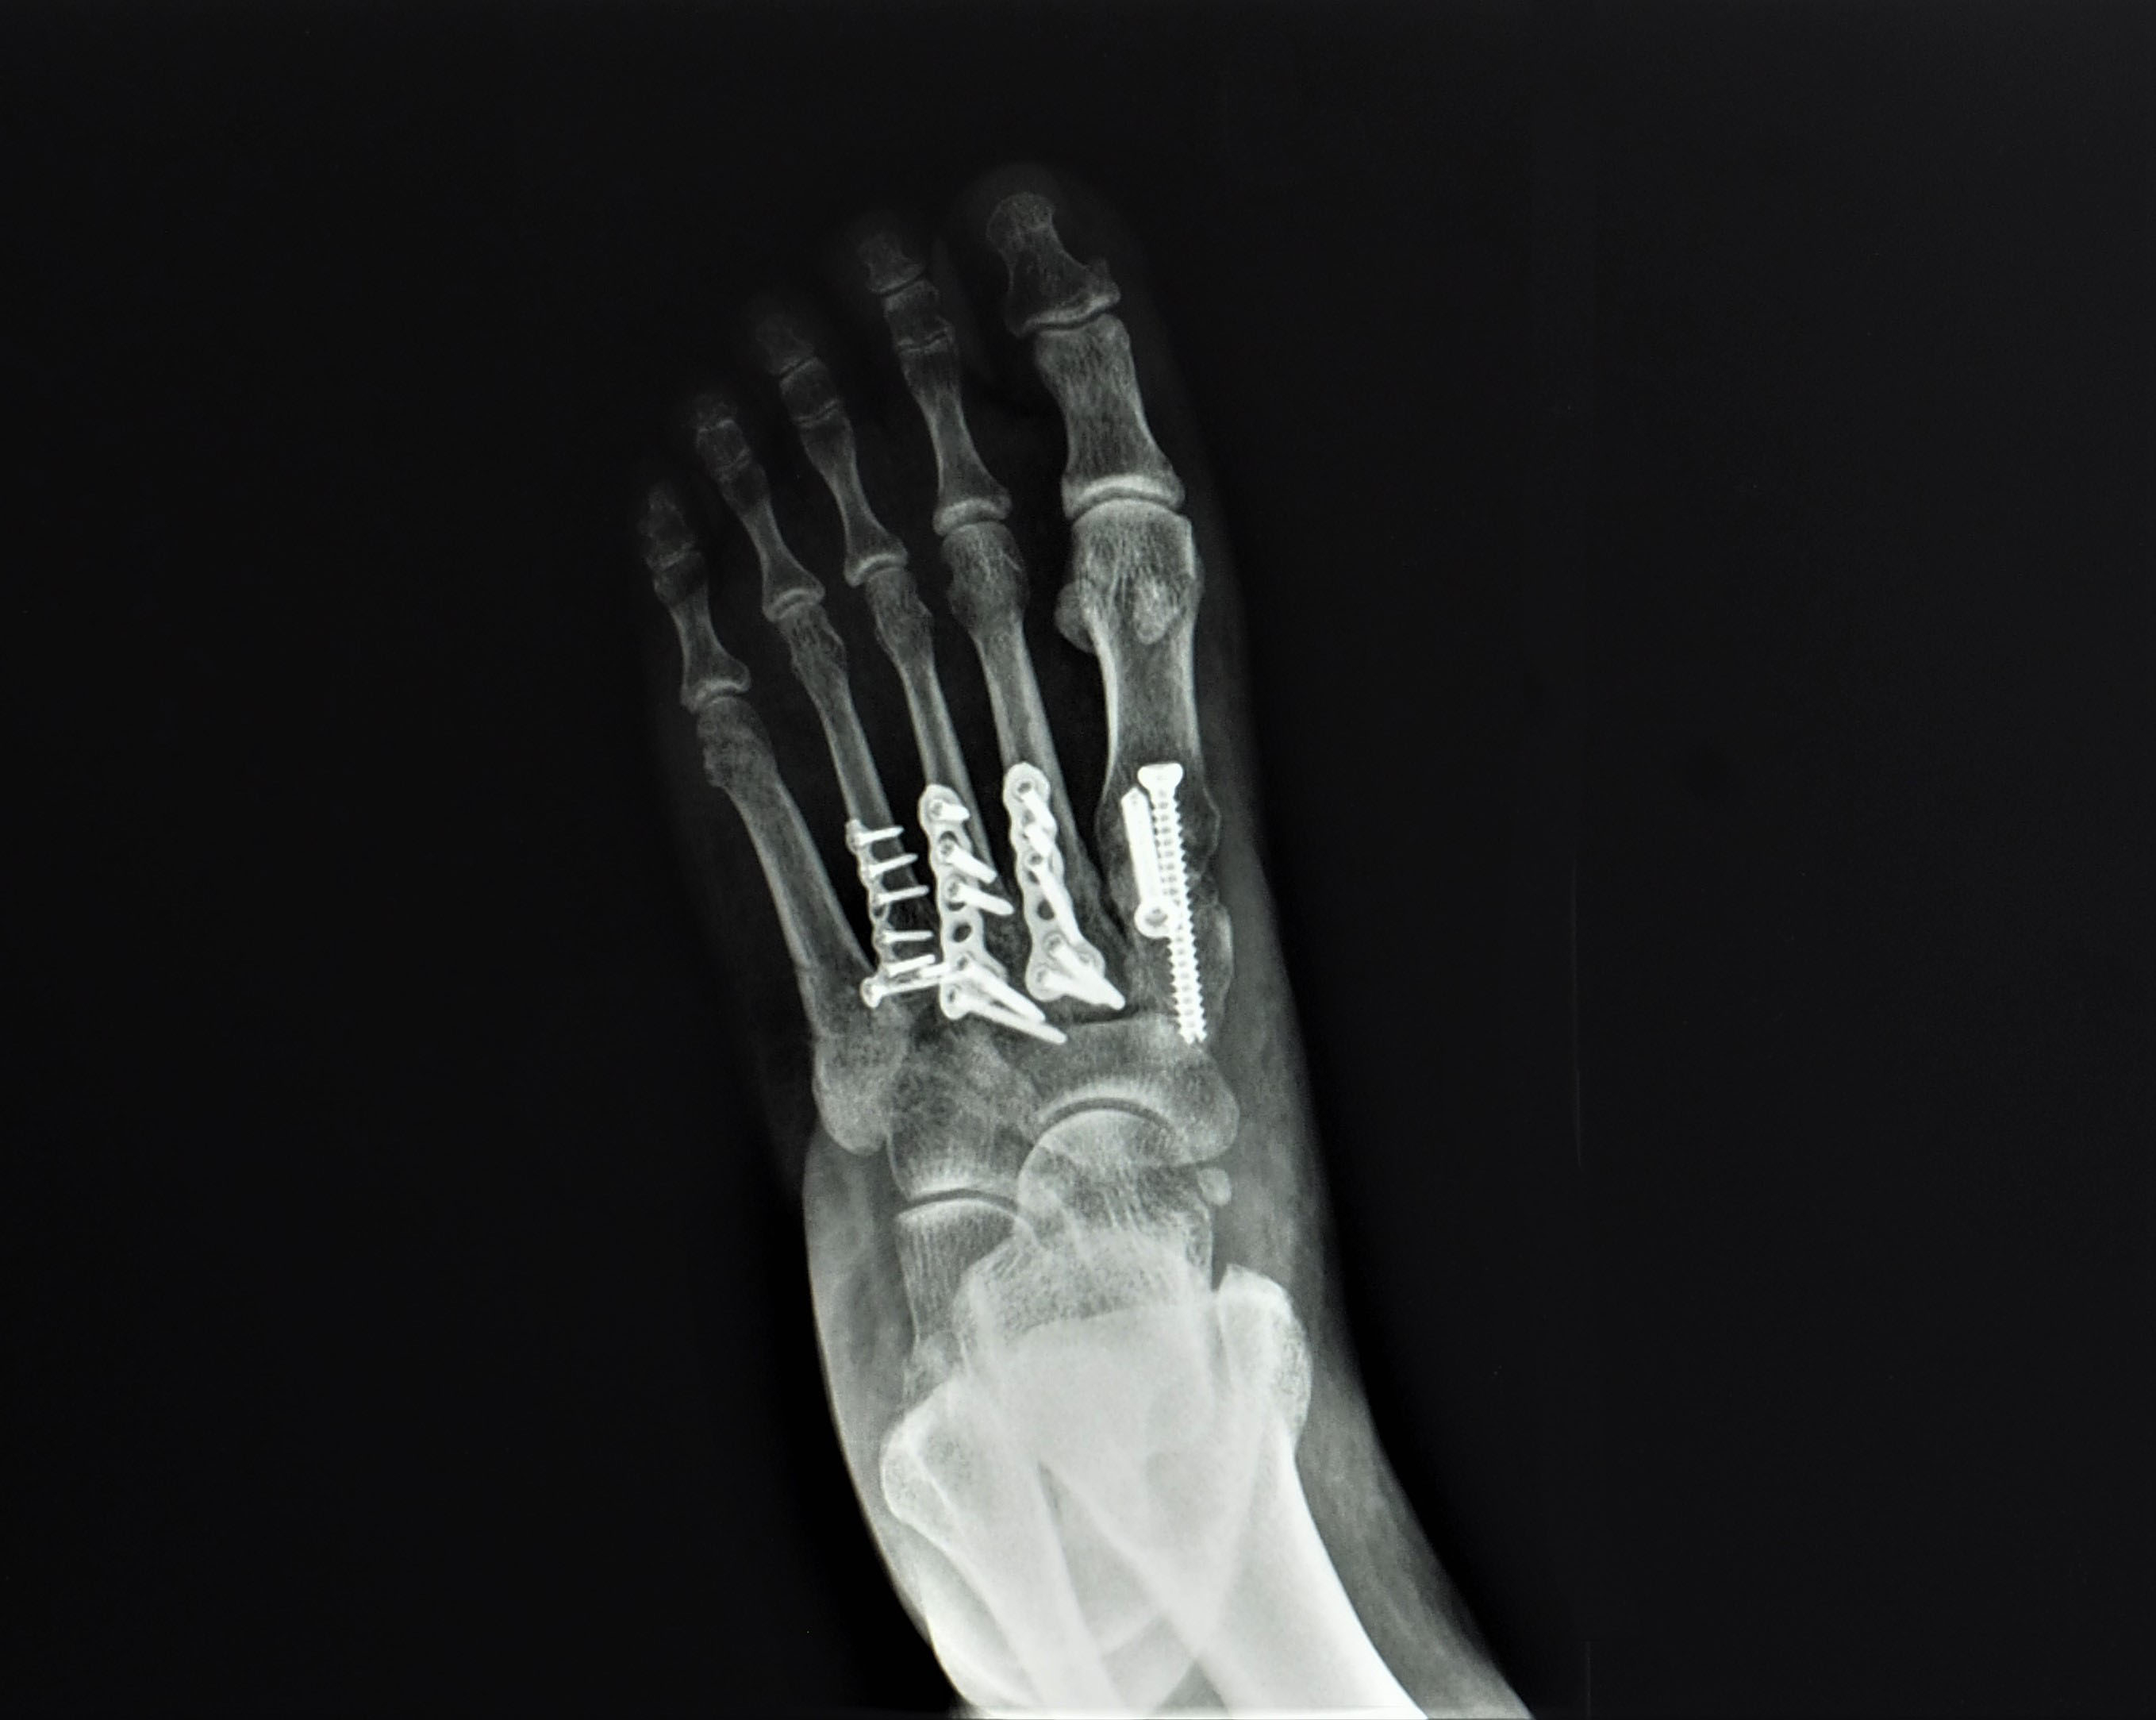

Stosowana dawniej przezskórna (bez rozcinania skóry i bezpośredniego dostępu do stawu) stabilizacja drutami Kirschnera obecnie jest już stosowana w wyjątkowych sytuacjach. Udowodniono, że przy zastosowaniu tej metody nie jest możliwe osiągnięcie prawidłowego nastawienia kości. Dlatego obecnie stosuje się leczenie na otwarto, z możliwością wizualnej kontroli ustawienia. W zależności od stopnia uszkodzenia stawu Lisfranca stosuje się jedno, dwa lub trzy cięcia skórne. Po nastawieniu kości należy je ustabilizować za pomocą płytek, śrub lub grotów Kirschnera.